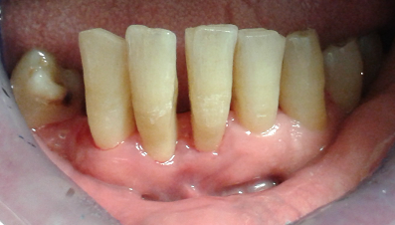

Descriviamo il caso di un paziente maschio di 56 anni con diagnosi di parodontite moderata generalizzata (Figg. 1-3), affetto da Diabete Mellito II in fase di scompenso (HbA1C 8,4%). Oltre alla malattia diabetica diagnosticata da 12 anni, il paziente presentava in anamnesi insufficienza renale, pregresso infarto miocardico acuto e storia di ipertensione arteriosa. I dati anamnestici hanno guidato la scelta dell’iter terapeutico da parte del team odontoiatrico.

In sede di valutazione clinica, il paziente presentava una scarsissima igiene orale e si evidenziavano evidenti segni di flogosi gengivale a causa di notevoli depositi di tartaro sopragengivale e sottogengivale, che rendevano difficoltoso un accurato esame parodontale. Successivamente, si è proceduto alla discussione in team circa la necessità di un intervento terapeutico personalizzato ed efficace che prendesse anche in esame la scarsa disponibilità emotiva e psicologica del paziente ad affrontarlo. Nel presente caso clinico l’adherence è stata considerata come un processo in continuo divenire. Adottando un approccio mutuato dal metodo biopsicosociale5 in una fase preliminare, un primo colloquio è stato svolto con il coniuge del paziente, al fine di instaurare un percorso riabilitativo di salute orale che fosse supportato anche dal caregiver.